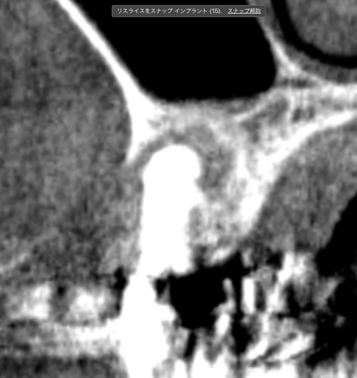

レントゲン写真でも理想的な位置

に埋入できました。

術前ではインプラントを埋入する骨組織はほとんど有りませんが、

術後完全に骨内に埋入出来ました。